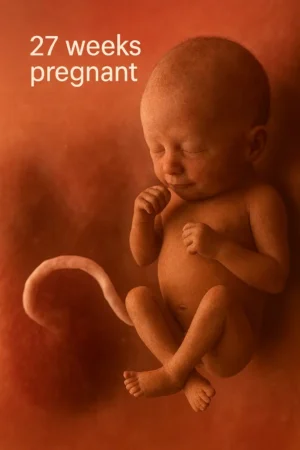

At 27 weeks pregnant, your baby is growing quickly and continuing to develop some crucial systems. Here’s what’s happening:

Your baby is about the size of a head of cauliflower or acorn squash, measuring roughly 14 inches long and weighing around 2 pounds. This is the stage where your little one is rapidly gaining weight and filling out. It’s exciting to think about how much bigger they’ll get in the coming weeks!

Your baby’s brain is developing rapidly, and their brain wave patterns are beginning to resemble those of a newborn. It’s amazing to think that their brain is already working hard to prepare for the outside world.

Your baby’s eyes can now open and close, and they can perceive light and darkness. Their hearing is becoming more refined, so they can recognize familiar sounds, including your voice and your partner’s. I remember talking to my baby during this time and imagining how it must feel for them to hear my voice from the inside.

Fetal Movements

Expect to feel more pronounced movements, such as kicks, turns, and stretches. You might also notice rhythmic, jerky movements — those are likely your baby’s hiccups! At 27 weeks pregnant, your baby’s movements are becoming more coordinated, and it’s exciting to feel them become more active.

Lungs and Breathing

Your baby’s lungs are continuing to develop and produce surfactant, a substance that helps the air sacs inflate after birth. While your baby still has some maturing to do, their lungs are getting stronger every day, and they’re preparing to take their first breaths once they arrive.